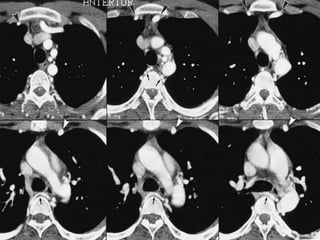

Bronchial artery embolization